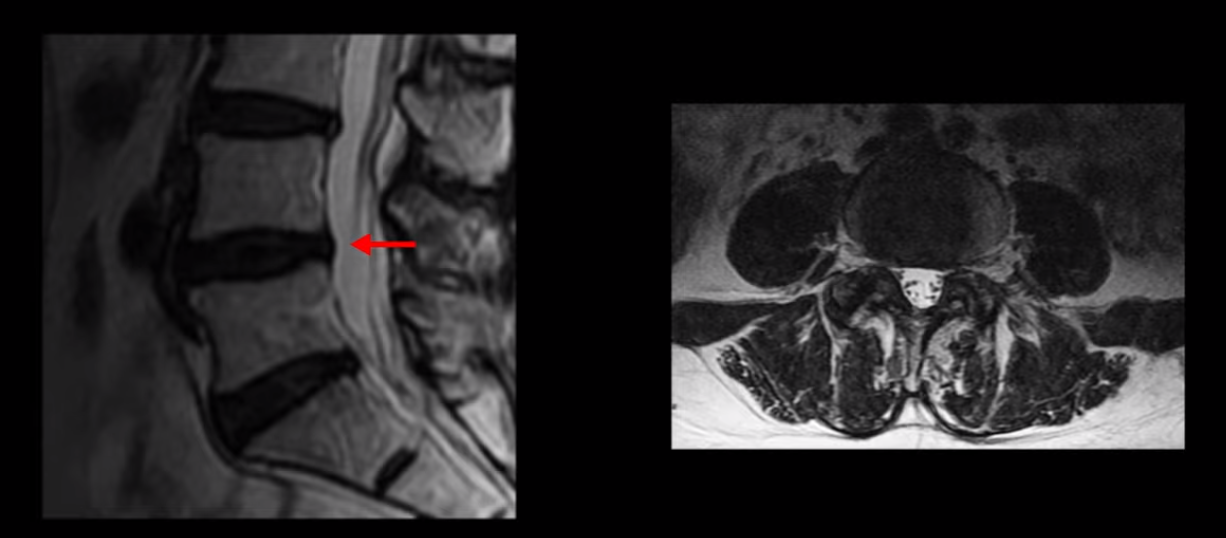

이분 MRI를 보시면 허리 세 마디가 퇴행은 있으나

4번 5번

전부 다 충분히 넓고 왼쪽 다리 쪽으로 신경이 나가는 추간공도 전부 다 충분히 넓은 상태입니다.

신경이 눌려 보이지 않는 겁니다. 그러니까 수술 후 MRI를 보고 모든 병원이 전부 다 ‘수술은 잘돼 있다’, ‘아무것도 해줄 게 없다’ 그냥 기다리라고만 얘기했다고 합니다. 신경외과, 정형외과, 재활의학과가 서로 다른 과로 전과시키면서 다들 아무것도 해줄 게 없다고 하니 희망을 잃은 상태였다고 했습니다.